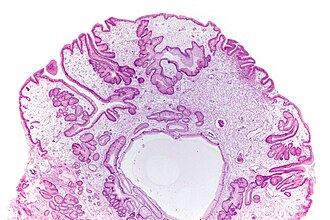

Juvenile polyp (stomach). H&E stain. | |

eroded, smooth or lobulated surface, pedunculated, increased lamina propria (LP) +/- edema, cystically dilated gland, +/-inflammation |

- Eroded, smooth or lobulated surface.

- Pedunculated.

- Increased lamina propria (LP) +/- edema.

- Cystically dilated gland.

- Often inflammed.

Mnemonic DIES = dilated glands, increased LP & inflammation of the LP, eroded/smooth surface, stalk.